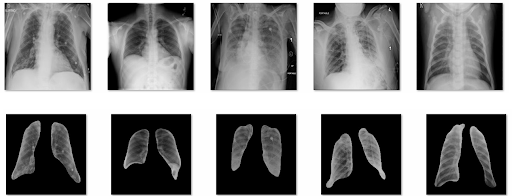

Ground Truth CT Scans

Segmented Lung Images